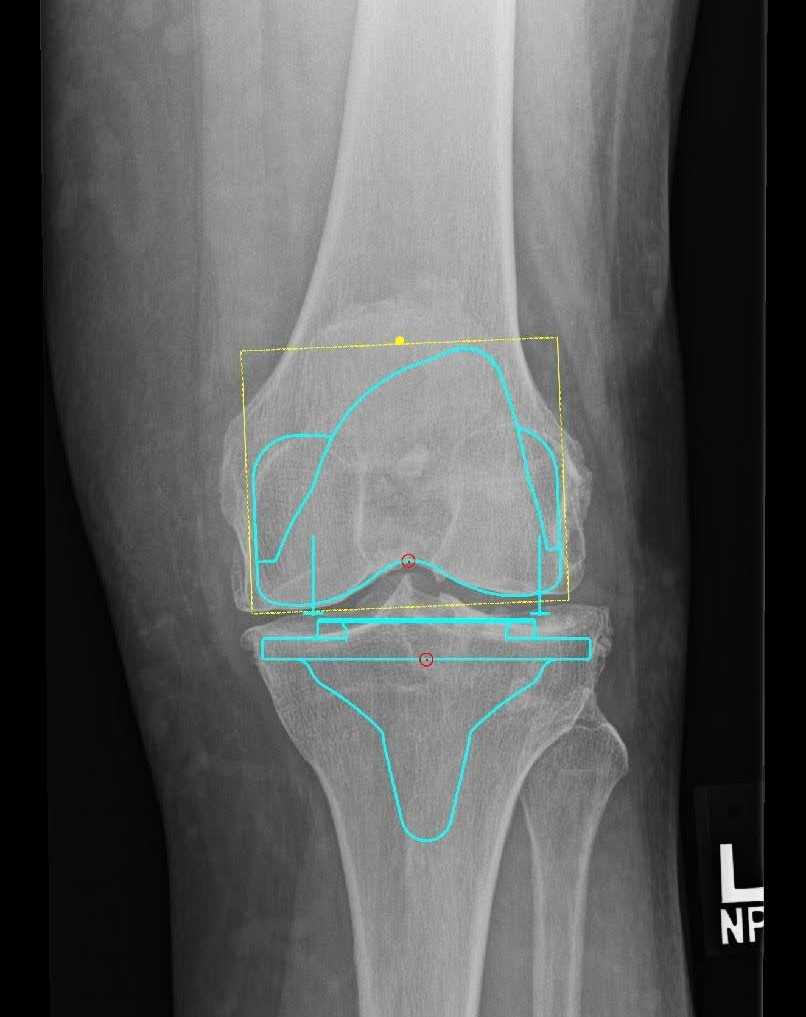

Pre-op X-Rays

Figure 1. Pre-op x-rays.

Equipment

- Attune system with a size 4 femoral component

- Size 5 tibia with 4x7 fixed bearing cruciate retaining insert

- 38 mm all polyethylene patellar button